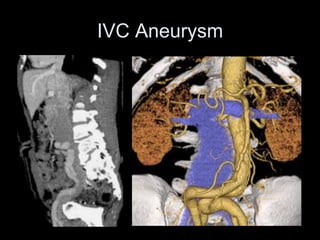

IVC Aneurysm

• Rare

• Saccular > fusiform

• Cause unknown, may be related to anomalous

connections in embryologic venous systems

– Acquired (trauma, AV fistulae)

– May be associated with other congenital CV

anomalies

• Sx: Thrombosis (7/16), pain, rupture, leg

swelling

– Massive penile bleeding (1/16)

– PE if thrombus